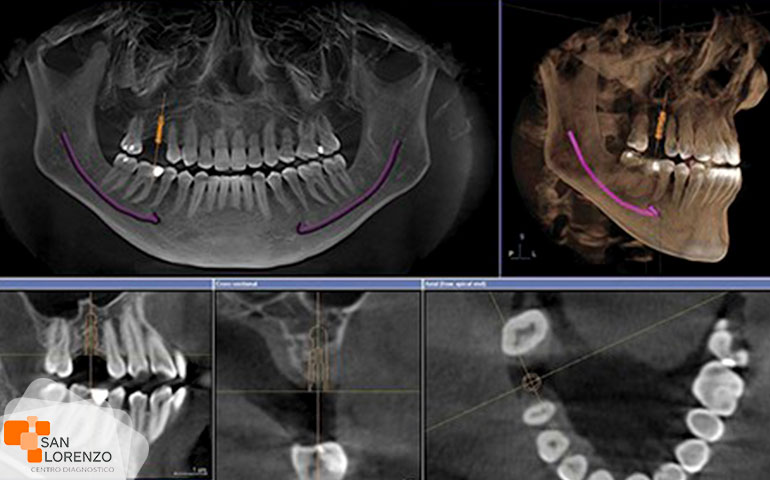

Actualmente en centro de diagnóstico San Lorenzo, la tomografía nos permite definir los detalles de la anatomía ósea. Este método nos ofrece las imágenes de anomalías de huesos, fracturas, tumores óseos, patologías relacionadas con la artrosis.

Los exámenes de imagenología que pueden incluirse para su diagnóstico pueden ser desde una radiografía, resonancia magnética, y tomografía axial computarizada. Este último tipo de examen lo aplicamos en nuestro centro de diagnóstico de calle Astorga 58 en Rancagua. En el caso de la radiología de mandíbula, es un método diagnóstico cómodo y barato. Se pueden detectar y evaluar las desviaciones en el aparato mandibular, tal estructura y función como morfología y relaciones conjuntas. En el caso de nuestro examen de escáner o tomografía axial computarizada, se utilizan como examen por lo general para establecer un diagnóstico más preciso. Actualmente, tenemos a disposición este tipo de examen de tomografía, para definir los detalles de la anatomía ósea. Este método nos ofrece imágenes con mayor detalle sobre anomalías de huesos, por mencionar algunos; la anquilosis, fracturas, tumores óseos y la artrosis.